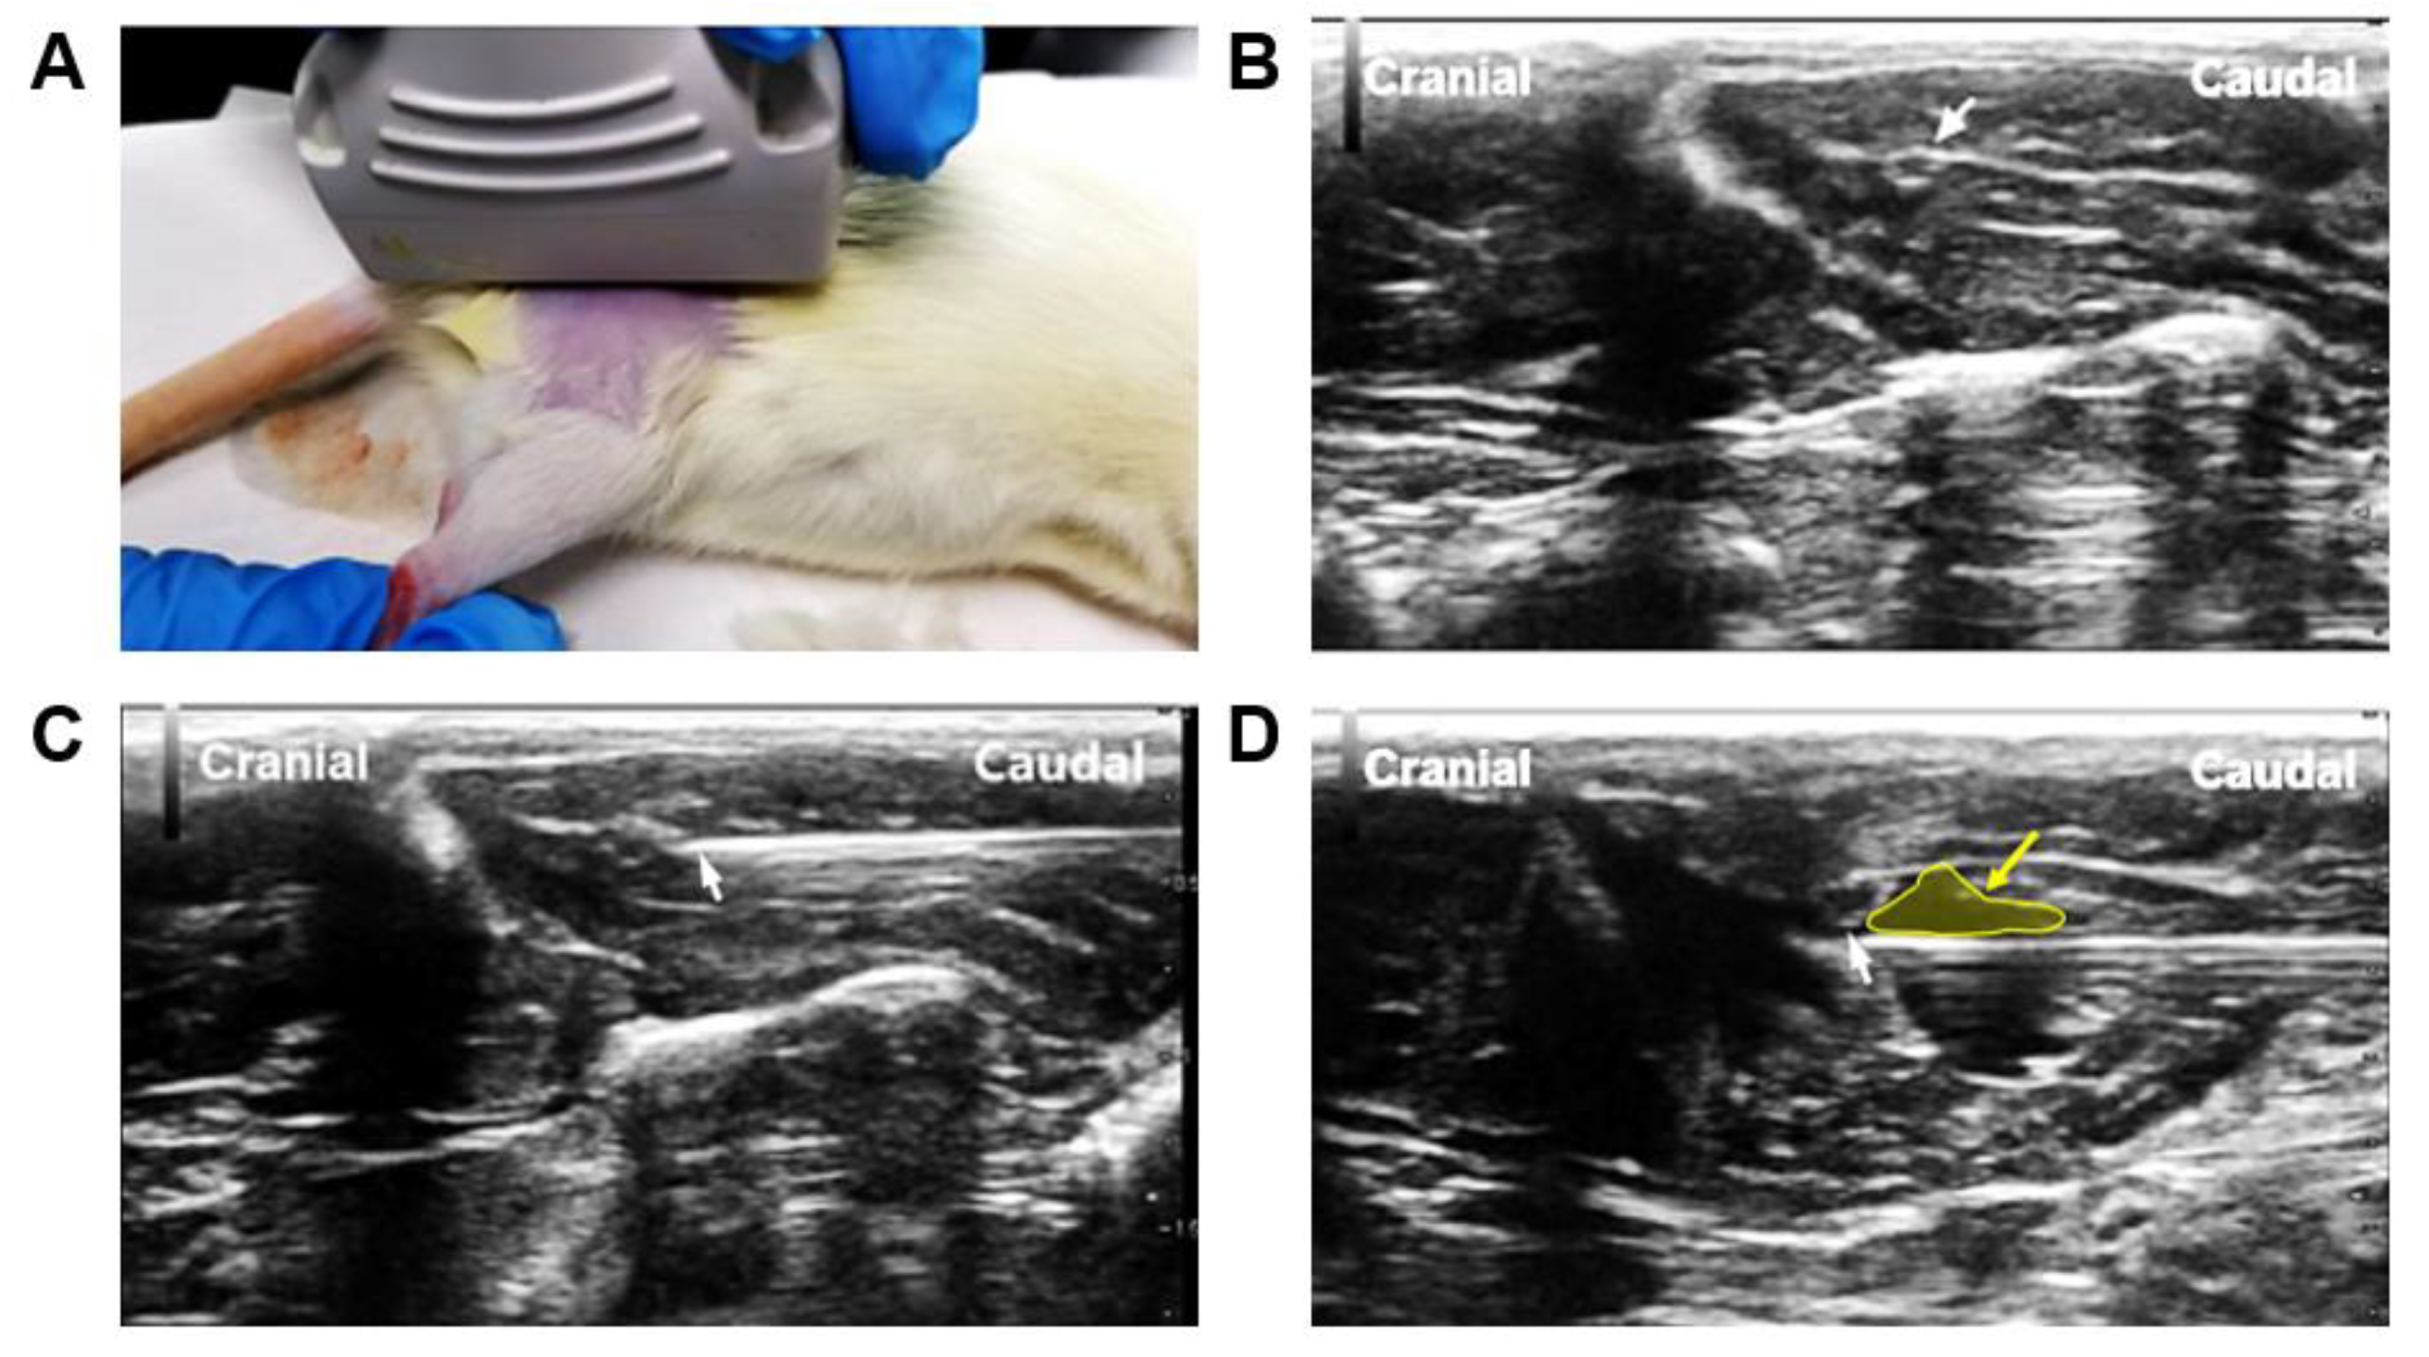

3.1. Assessment of Pain and Neuroma Formation